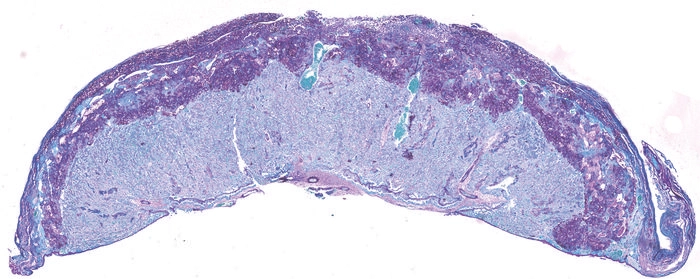

Mice with B. breve in their gut lost fewer of their pregnancies (Image credit: University of Cambridge).“Our results open up an entirely new way to assess the health of a pregnant mother and her developing fetus by looking at the mother’s gut microbiome,” says Dr. Jorge Lopez Tello, first author of the report, who carried out the work while at the University of Cambridge’s Department of Physiology, Development and Neuroscience.

Those with the bacteria lost fewer pregnancies, and their placenta was better able to absorb and transport nutrients, such as amino acids and lactate. The placenta also made other essential hormones, like prolactins and pregnancy-specific glycoproteins.